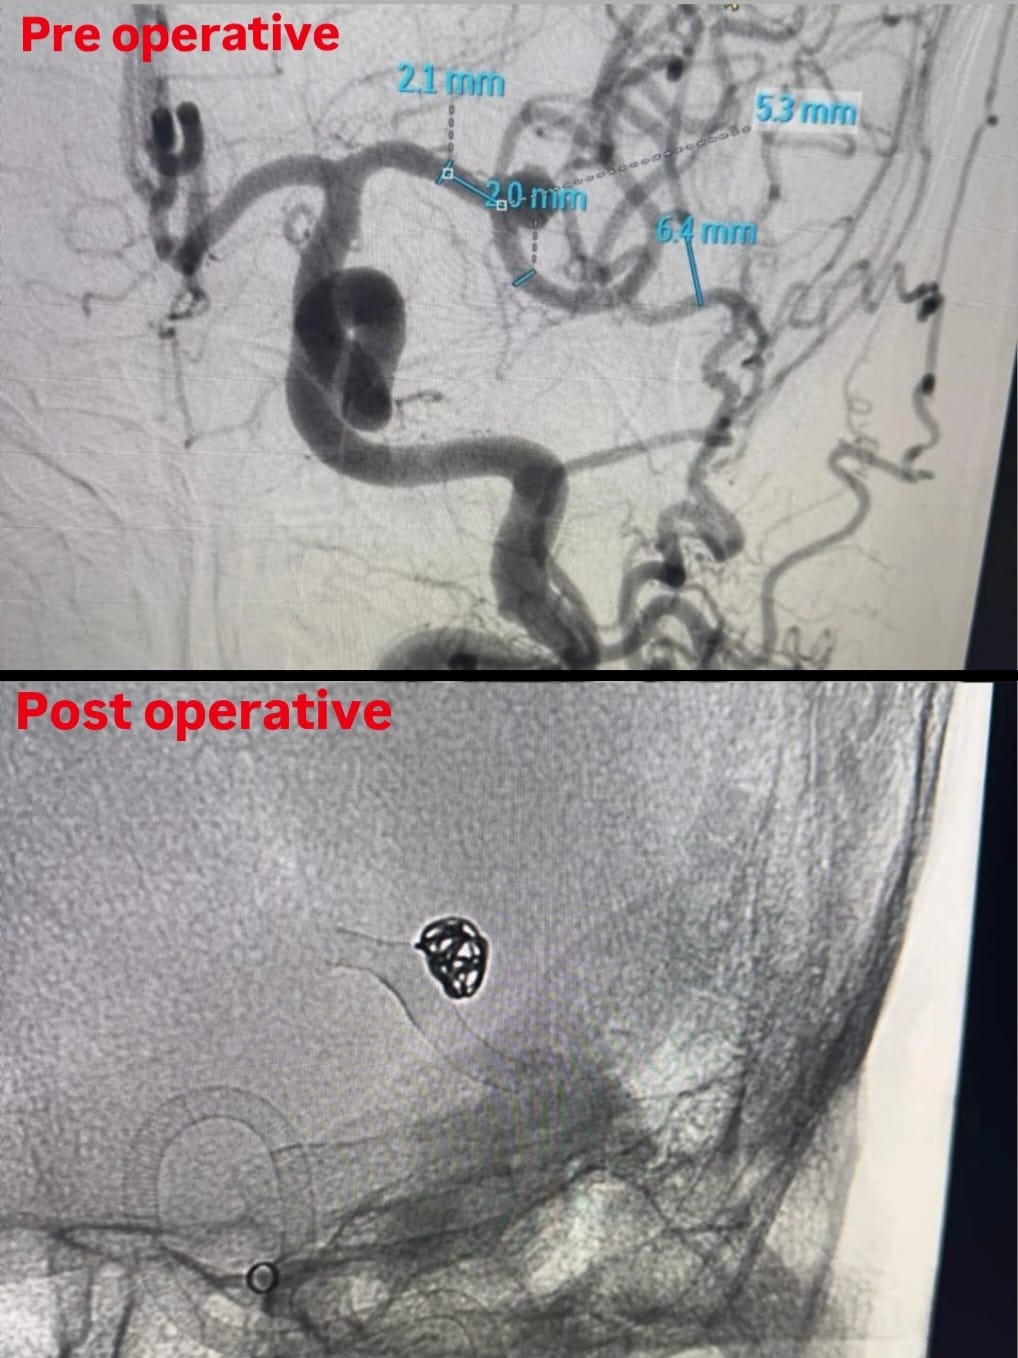

Aneurysm coiling

मेंदूच्या रक्तवाहिनीची अवाजवी वाढ काय आहे?

मेंदूच्या रक्तवाहिनीची अवाजवी वाढ ही अशी परिस्तिथी आहे ज्यामध्ये मेंदूतील कमकुवत क्षेत्रात धमन्यांच्या भिंतींजवळ सूज किंवा फुगवटा निर्माण होतो. हृदयातून शरीराच्या वेगवेगळ्या भागात रक्त पोहोचवणार्या नलिकांना धमनी म्हणतात .मेंदूच्या रक्तवाहिनीची अवाजवी वाढ मेंदूत कुठेही होऊ शकत असली तरी विशेषतः त्या क्षेत्रामधे होण्याची शक्यता जास्त असते जिथे रक्त वाहिन्यांचे विभाजन होते.

निदान आणि उपचार कसे केले जाते? आपल्याला समजणारे पहिले लक्षण म्हणजे अचानक आणि असह्य डोकेदुखी आहे ज्याच्या उपचारासाठी डॉक्टर वैद्यकीय इतिहासाची आणि शारीरिक तपासणी करतात. रप्चर न झालेले एन्युरिझम आणि मेंदूतील रक्ताचा गळती निश्चित करण्यासाठी, एमआरआय आणि सीटी सारख्या इमेजिंग चाचण्या डॉक्टर सुचवू शकतात. लक्षणे असलेल्या रप्चर झालेल्या एन्युरिझम चे सीटी स्कॅनवर नकारात्मक परिणाम आल्यास, लंबर पँचर (जेथे सेरेब्रोस्पायनल फ्लुइडचा नमुना गोळा केला जातो आणि रक्त तपासले जाते) केले जाते. रक्तवाहिन्यांच्या समस्येचे निराकरण करण्यासाठी डिजिटल सबस्ट्रॅक्शन अँजियोग्राफी (डीएसए-DSA) देखील केली जाते.

मेंदूच्या रक्तवाहिणीची अवाजवी वाढ चा आकार, स्थान, लक्षणे आणि तीव्रतेनुसार उपचार वेगवेगळे असतात. प्रत्येक व्यक्तीसाठी औषधं आवश्यक नाही. रप्चर ची जोखीम कमी असल्यास, नियमित तपासणी करून व्यक्तीचे काळजीपूर्वक परीक्षण केले जाते. रप्चरची शक्यता कमी करण्यासाठी जीवनशैलीतील बदल जसे धूम्रपान सोडणे किंवा उच्च रक्तदाबाचा उपचार करण्याचा सल्ला दिला जातो. अनरप्चर्ड ब्लेबसाठी सामान्यत: औषधं दिली जातात. शस्त्रक्रिया रप्चर झालेल्या अवाजवी वाढ झालेल्या रक्तवाहिनीचे आणि रप्चरपासून बचाव करण्यास मदत करते. शस्त्रक्रियेमध्ये वाढलेल्या रक्तवाहिन्यांमधे स्प्रिंगसारखी जाळी बसवली जाते ज्यामुळे त्याचे रप्चर टाळता येते किंवा उष्णतेची उर्जा वापरता येते आणि वाढलेल्या रक्तवाहिन्या काढून टाकून आसपासच्या रक्तवाहिन्यां जोडल्या जातात.

असेच एक ७६ वय वर्षाचे आजोबा आणि ६५ वय वर्षाच्या आज्जी आमच्या लाईफ लाईन हॉस्पिटल, कोल्हापूर मध्ये ऍडमिट झाले होते. त्याची अधिक तपासणी करून त्यांना डॉ संदीप इंचनाळकर( मेंदू व मणका विकार तज्ञ) यांनी ऑपरेशन चा सल्ला दिला. पेशंट च्या नातेवाईकांनी लगेच निर्णय घेवून ऑपरेशन साठी होकार दिला. त्यानंतर इंचनाळकर सरांनी दोन्हीही पेशंट ची ऑपरेशन यशस्वीरीत्या केलेत आणि त्यांना त्या आजारातून मुक्त केले. आता ते दोन्हीही पेशंट अगदी आपल्या पहिल्यासारखे जीवन जगत आहेत.